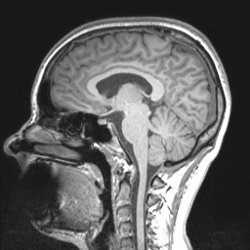

MRT

Neuroradiologie